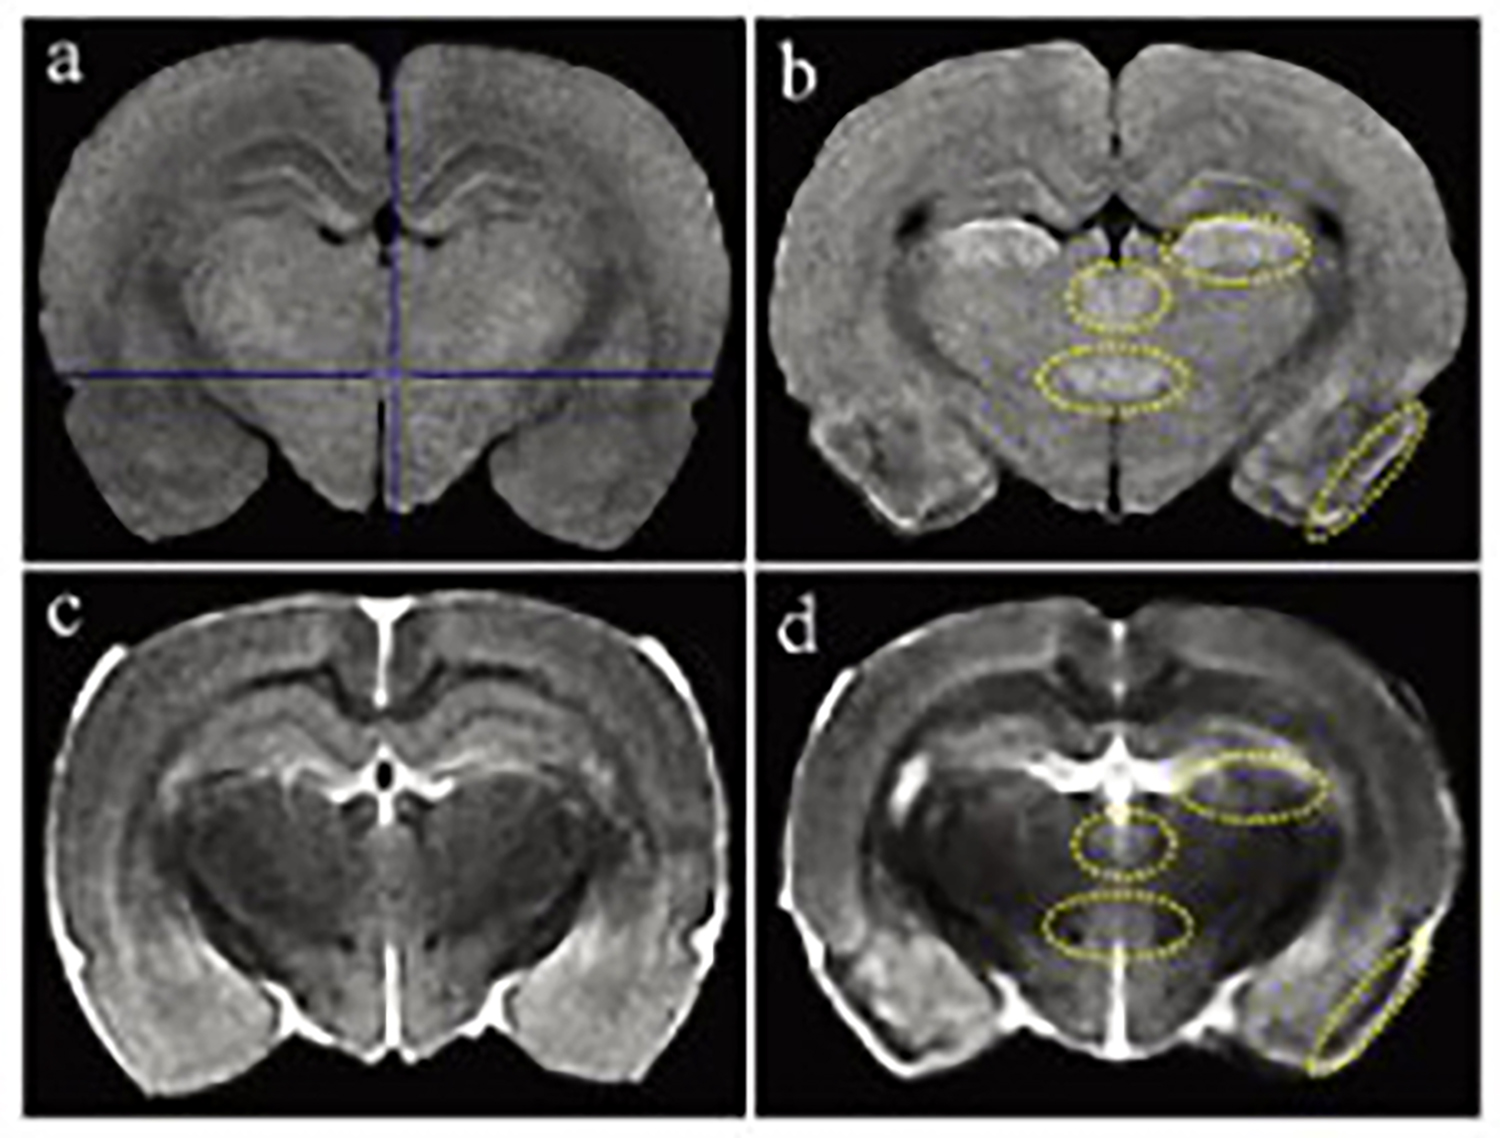

磁共振成像(MRI)广泛应用于临床前研究和药物开发,是一种强有力的无创性方法,可用于评估小鼠疾病模型的表型和治疗效果。

小动物磁共振成像(MRI)是一种强大的非侵入性工具,可用于检测临多种病变。

一个新的紧凑型高性能小动物磁共振成像平台(M3),该系统使用一种新的磁铁设计和一套相关的软件,降低了小动物磁共振成像仪的成本和复杂性。